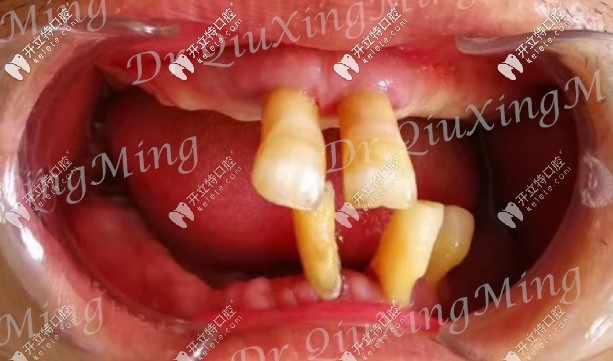

首先看下他的牙齒情況:嘴里還剩下5顆牙,還有2顆殘根,邱醫(yī)生建議全部拔掉,因?yàn)槟?顆牙也已經(jīng)松動(dòng)了,沒(méi)有保留的必要。

大爺口腔剩余牙齒圖